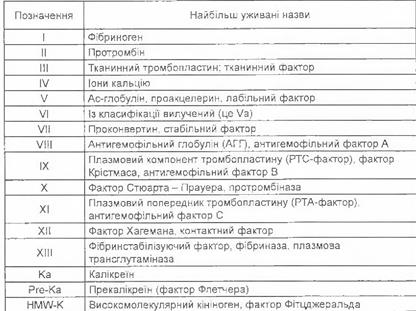

Г емостаз – це сукупність фізіологічних процесів, які завершуються зупинкою кровотечі при пошкодженні судин.

Зупинку крові забезпечують фактори:

- судинний;

- активні речовини плазми;

- активні речовини формених елементів крові.

Фактори згортання крові

Судинно – тромбоцитарний механізм згортання крові

Ø рефлекторний спазм судини;

Ø адгезія тромбоцитів;

Ø зворотня агрегація – утворюється рихла тромбоцитарна пробка, яка пропускає плазму крові

Ø незворотня агрегація – непрониклива для плазми\ під дією тромбіна, який міняє структуру тромбоцита\

Ø ретракція тромбоцитарного тромба \ ущільнення тромба за рахунок тромбостеніна.\

Коогуляційний гемостаз

1 ФАЗА – формування протромбінази:

Ø пошкоджена стінка виділяє тромбопластин + пошкоджуються клітини крові і виділяється

тромбоцитарний і еритроцитарний тромбопластин;

Ø в результаті взаємодії з 7,5,10 факторами та з участю кальцію утворюється протромбін аза.

2 ФАЗА

Утворення тромбіну. Фаза короткочасна 2-5 с.

Ø протромбіназа адсорбує на собі протромбін і перетворює його в тромбін;

Ø протікає під впливом 5,10, факторів згортання крові + кальція.

3 ФАЗА

Перетворення тромбіну в фібрин.

Тромбін діє на фібриноген і переводить його в активну форму – фібрин.